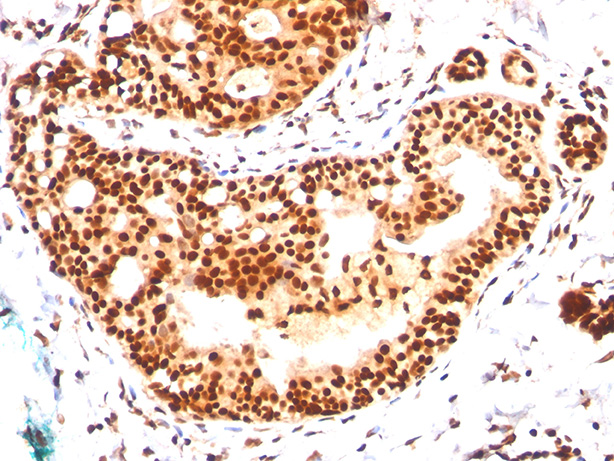

Formalin-fixed, paraffin-embedded human tonsil stained with SUMO-2 MAb (SM23/496) |